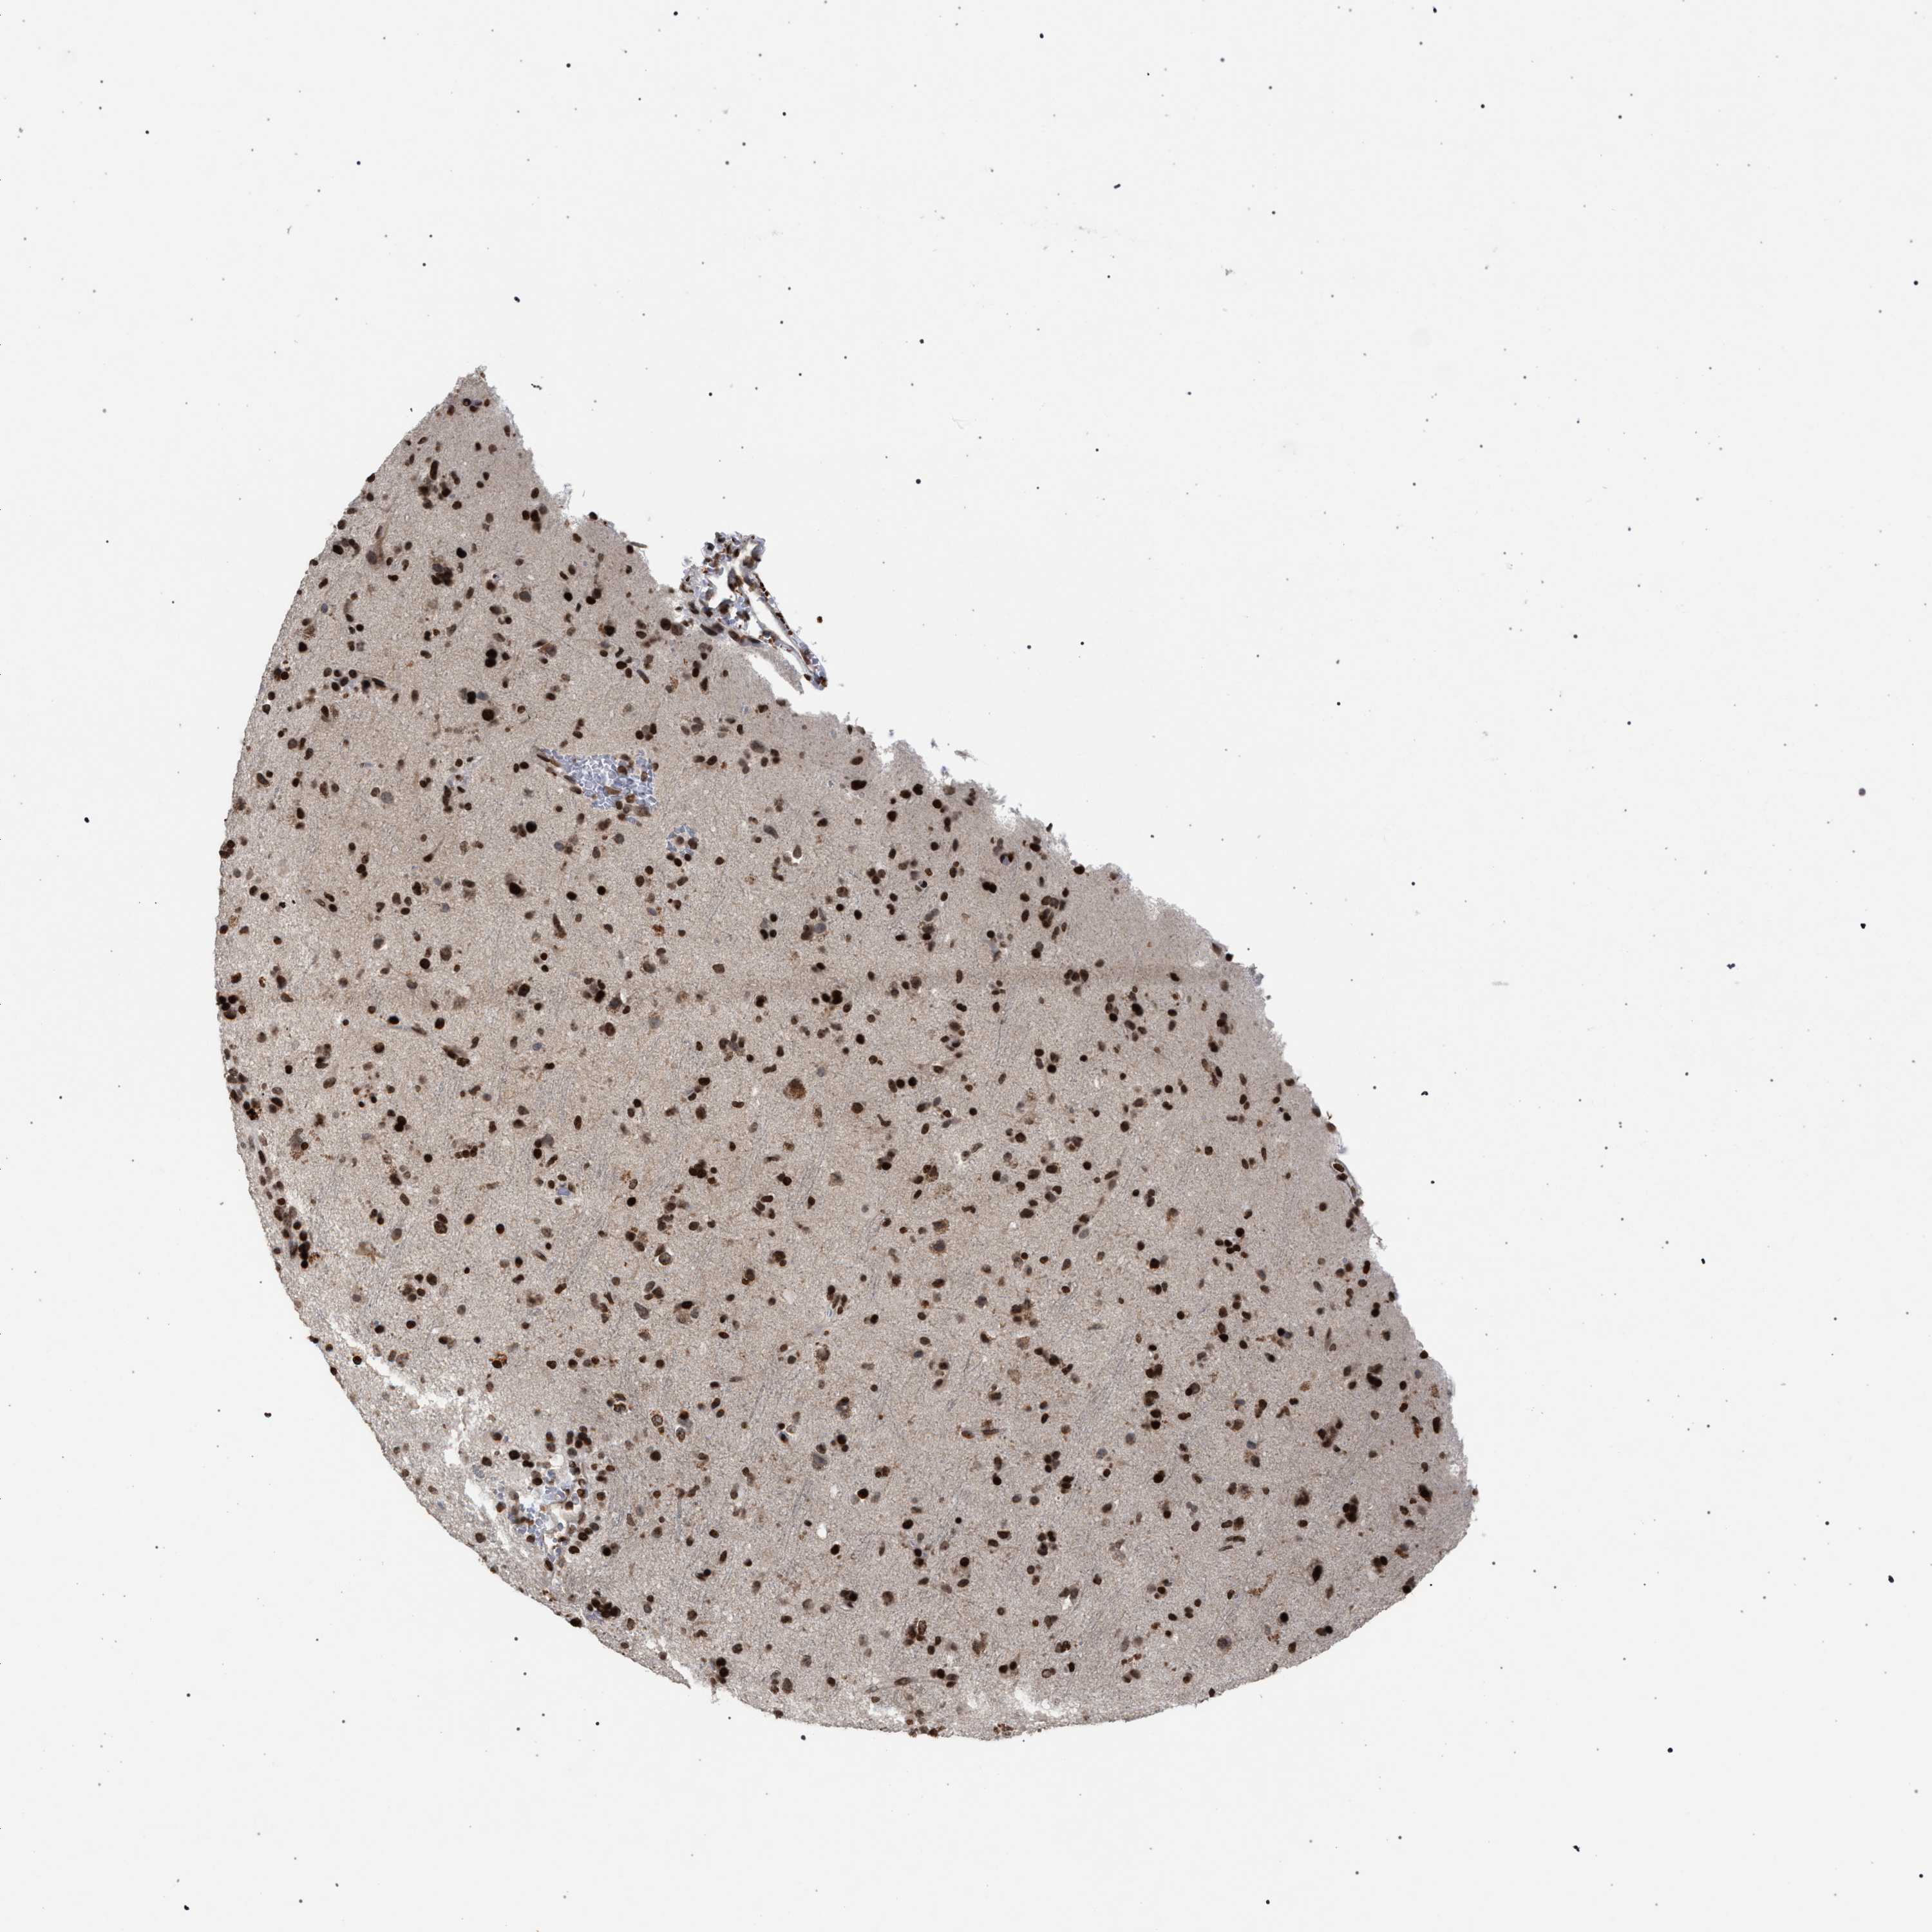

GLIOMA - Protein expressioni

A mouse-over function shows sample information and annotation data. Click on an image to view it in a full screen mode. Samples can be filtered based on level of antibody staining by selecting one or several of the following categories: high, medium, low and not detected. The assay and annotation is described here.

Note that samples used for immunohistochemistry by the Human Protein Atlas do not correspond to samples in the TCGA dataset.

Antibody stainingi

Antibody staining in the annotated cell types in the current human tissue is reported as not detected, low, medium, or high, based on conventional immunohistochemistry profiling in selected tissues. This score is based on the combination of the staining intensity and fraction of stained cells.

Each image is clickable and will lead to virtual microscopy that enables deeper exploration of all samples and also displays staining intensity scores, fraction scores and subcellular localization as well as patient and tissue information for each sample.

Antibody CAB022455

Staining

High

Medium

Low

Not detected

Intensity

Strong

Moderate

Weak

Negative

Quantity

>75%

75%-25%

<25%

None

Location

Nuclear

Cytoplasmic/membranous

Cytoplasmic/membranous,nuclear

Glioma, malignant, High grade

Glioma, malignant, Low grade